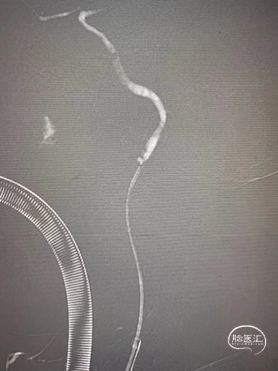

第五步处置:支架植入

观察到:1.颈动脉起始部医源性夹层形成。2.起始部球扩后内膜粗糙不完整,可能存在斑块碎裂及附壁血栓残留。3.基于以上分析,术者选择Wallstent 9-40支架。